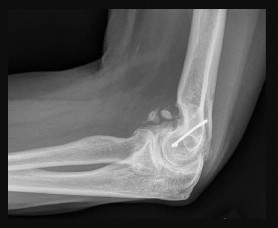

Question 8

A 30-year-old male presents with a slow-growing, deep-seated, painful soft tissue mass in his left foot near the ankle joint. Imaging reveals a heterogeneous mass with stippled calcifications. Biopsy demonstrates a biphasic pattern consisting of spindle cells and epithelial cells. Which of the following cytogenetic abnormalities is classically associated with this tumor?

Explanation

The clinical, radiographic, and histologic descriptions are classic for synovial sarcoma. Synovial sarcoma is characterized by the specific chromosomal translocation t(X;18)(p11;q11), which results in the SYT-SSX fusion gene. This molecular marker is highly sensitive and specific for confirming the diagnosis.